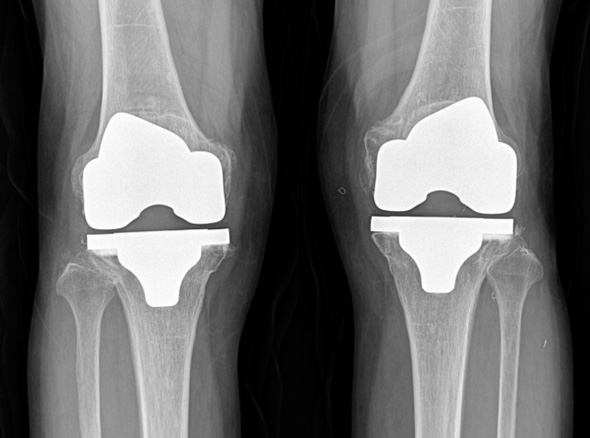

세계적인 의료기기 기업 스트라이커(Stryker)사의 특화된 임플란트를 사용합니다.

정밀한 설계, 내구성, 생체 적합성 등의 장점을 두루 갖추어 전 세계적으로 가장 많이 사용되고 있습니다.

최대한 가볍고 오래 사용 가능하며 알러지를 거의 유발하지 않는 인공관절을 사용합니다.